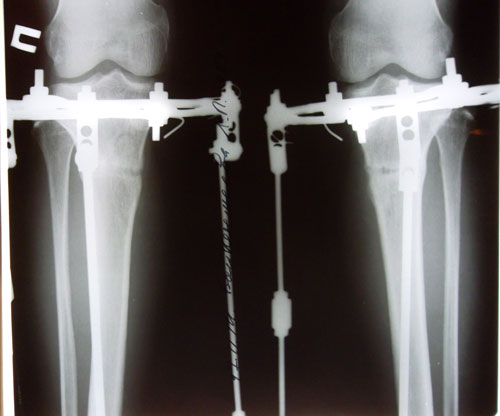

Рентген в день снятия аппаратов.

Вложения

SAM_9350.JPG

SAM_9347.JPG